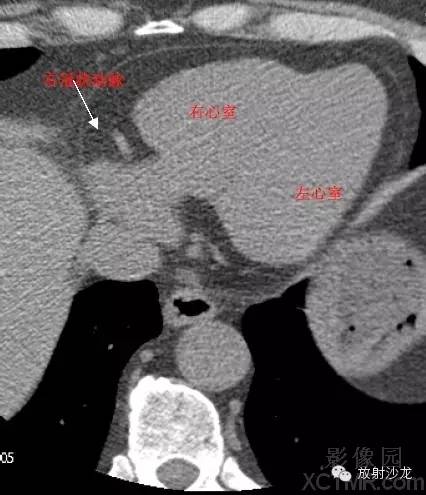

RA -Right Atrium右心房

LV -Left Ventricle左心室

RV -Right Ventricle右心室

RCA -Right Coronary Artery 右冠状动脉